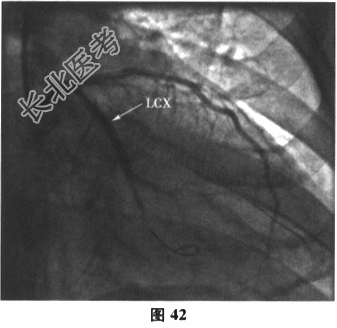

- 多项选择题6.[提示]运动负荷心电图试验示:最大运动功量3.3METs, Ⅱ、Ⅲ、aVF、V3~V4导联ST段压低0.05~0.1mV(图38)。查血小板聚集率:Ara14.57%, ADP36.55%。再次行冠状动脉造影:回旋支近端次全闭塞, LCX内支架内膜重度增生;LAD中段斑块浸润, 最重狭窄30%~40%,轻度肌桥压迫, 第二对角支狭窄70%;RCA近段斑块浸润, 如图39~图41所示。故于回旋支再次植入一枚支架(Promus Element2.75mm×38mm),如图42所示。